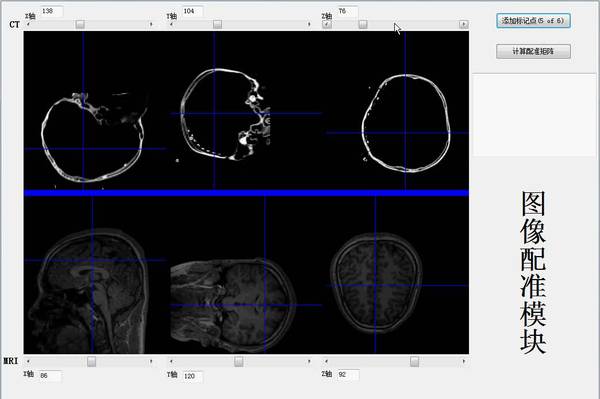

癫痫作为一种古老的神经系统常见病,严重危害着人类的健康。根据世界卫生组织的报告,全球癫痫患者约5000万人,而我国约有900多万癫痫患者,其中600万病人每年仍有发作,而且每年还会出现40万新发病例。近年来随着我国人口老龄化,脑血管病、痴呆和神经系统退行性疾病的发病率增加,老年人群中癫痫发病率已出现上升的趋势。从原理上讲,癫痫是由于大脑神经细胞的阵发性过度放电导致的。轻度的癫痫可以通过药物加以控制,然而一旦发展成为顽固性癫痫,药物治疗将很难起效或者引起不可接受的副作用。此时,如果癫痫病灶具有局灶性,即应考虑手术治疗。进行病灶切除手术前,必须进行病人的脑功能映射,从而确定病灶和必须保留的重要功能区域的位置。目前临床所使用的电刺激、fMRI、PET-CT等脑功能映射方法均存在各自的弊端,并且提供信息不够直观。针对这些不足之处,本作品提出了基于颅内脑电High Gamma(HG) 频段能量活动的个体化功能映射技术,并以此为基础建立了一套基于颅内脑电的高精度脑功能映射与神经监护系统。整个系统由5部分组成:(1)图像配准(2)电极坐标提取(3)MRI图像分割和重建(4)ECoG信号处理(5)显示控制界面。相比于如前所述的现有技术,本作品实现了个体化的脑功能映射3D可视化,主要具有三点优势:首先,通过分析执行任务时病人的脑电变化确定功能区,更加快速准确的实现了功能区的映射,避免了对人脑的电流刺激。第二,操作用时远远小于电刺激。完成一类功能映射,从开始测试到分析完结果平均需要5分钟。第三,功能映射结果直观地显示在病人自己的大脑结构上,并且可以任意地进行三维旋转和调整,为临床提供了方便直观的信息。本作品目前已成为清华大学第二附属医院癫痫中心在制定手术方案时的一个重要参考依据,并在中央电视台《走进科学》栏目的癫痫治疗专题节目中得到了展示。与此同时,目前市面上的颅内脑电监测系统均是波形监测,无法显示脑功能映射;而能够进行脑功能可视化显示的脑电地形图仪又均基于头皮脑电,且对所有病人的脑电数据均投射到标准脑模型上,不符合人体的特异性。综上所述,由于其实用性及独创性,本作品应具有较高的商业价值。